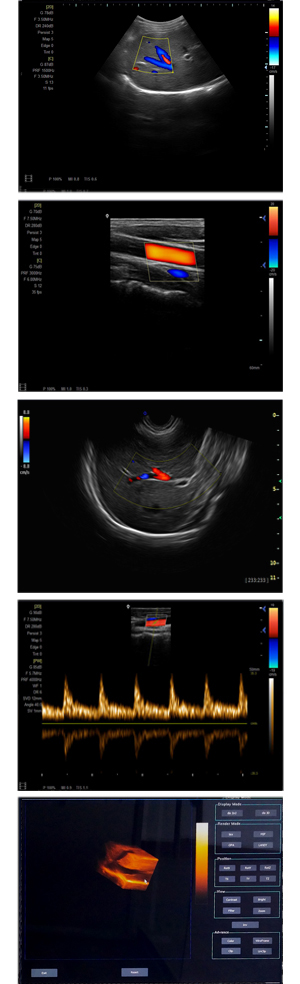

為高集成數(shù)字式彩色多普勒系列產(chǎn)品之一,廣泛實(shí)施于腹部,產(chǎn)科,婦科,血管,小器官,泌尿,新生兒和兒科等臨床,屬全身應(yīng)用型彩色多普勒儀器。

●全身應(yīng)用型包含2D/CFM/PDI/PW/ M等掃描模式;

●升級(jí)版可選配3D、反向諧波等高級(jí)功能。